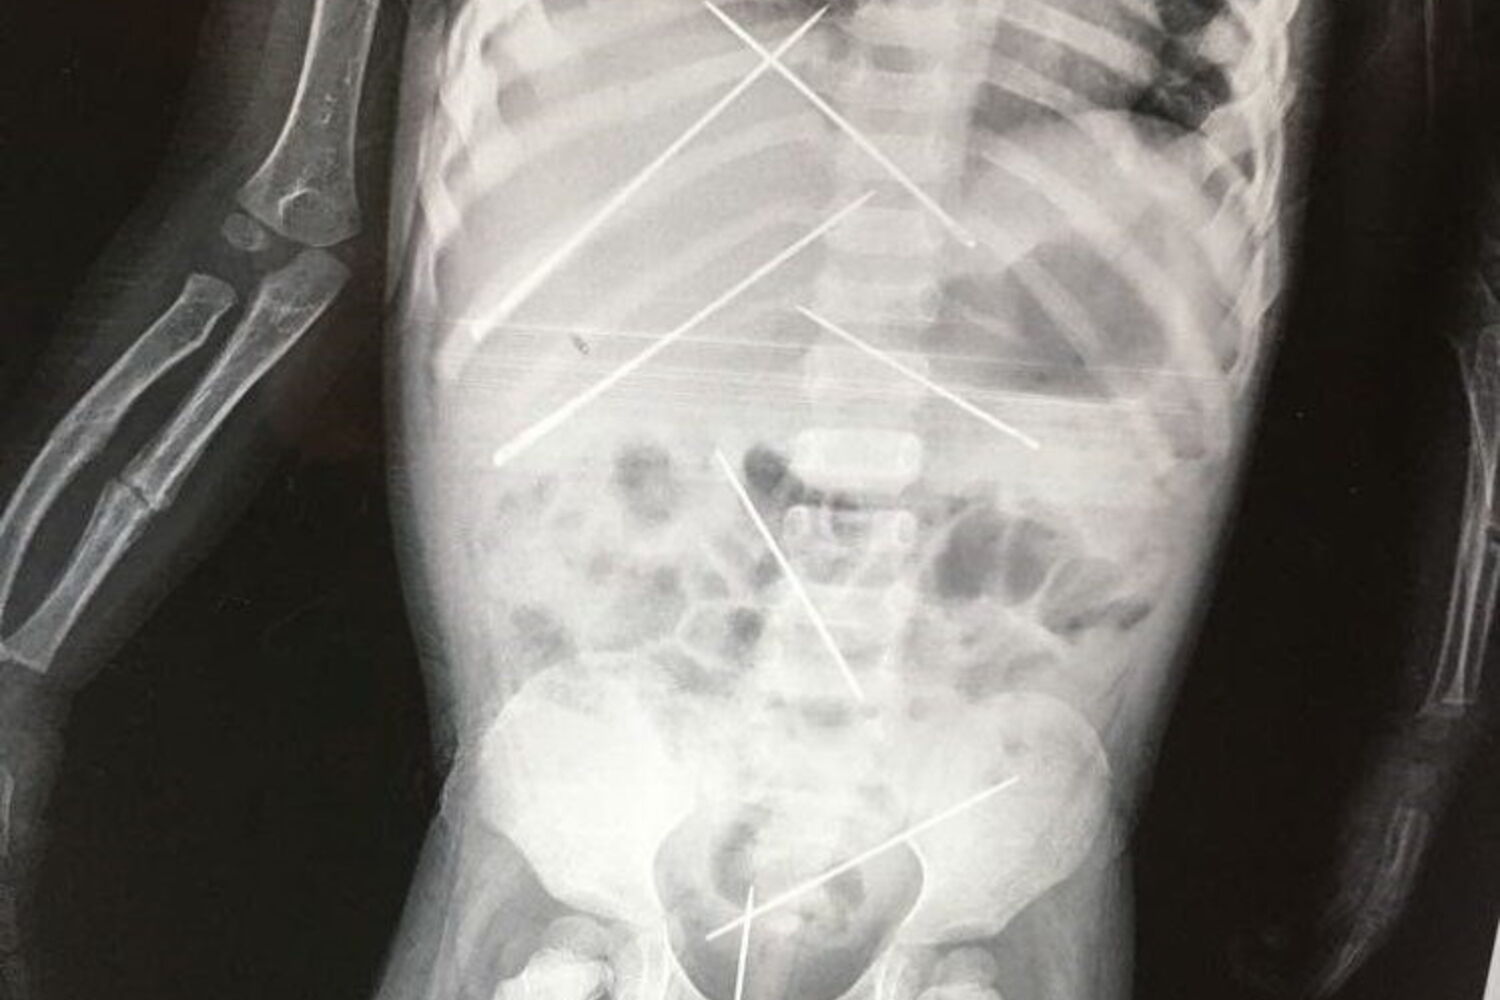

A criança de três anos tinha mais de sete agulhas no abdómen.

Um homem é acusado de fazer 'magia negra' a uma criança perfurando-a com agulhas, em Bankura, na Índia. Foram descobertas mais de sete agulhas no abdómen da vítima.

A criança foi assistida no Hospital SSKM, em Kolkata. Os médicos descobriram várias agulhas inseridas no corpo da vítima, que tinha também um braço partido.

Quando os médicos se aperceberam da gravidade do caso, decidiram não retirar as agulhas. Mantiveram-na durante dois dias sob observação, para decidir o que haveriam de fazer.

Foi operada e os médicos continuam a tentar estabiliza-la e ajudá-la a ultrapassar o trauma. De acordo com os médicos, a mãe da criança disse-lhes que as agulhas estavam dentro do seu corpo há mais de 15 dias.